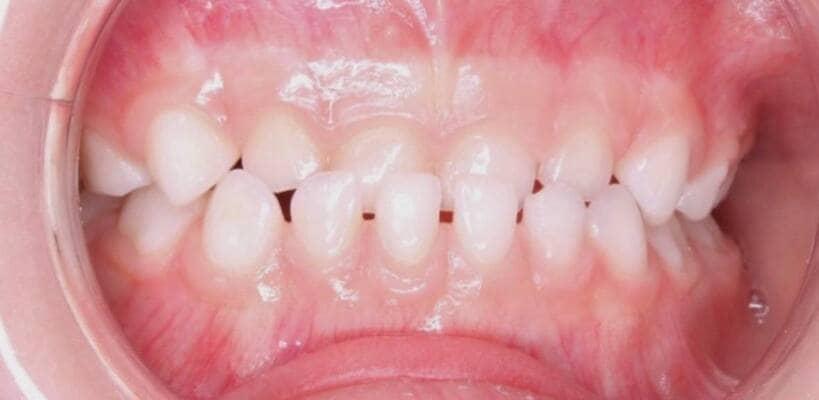

Один рік і два місяці вік дитини. Хтось скаже: «Що там тим зубам можна лікувати?!» Однак є ситуації, коли каріозний процес розвивається просто блискавично. Часто це пов’язано з порушеннями у формуванні твердих тканин ще внутрішньоутробно. А коли такі зубчики прорізуються, руйнування відбувається просто «на очах». Вісім із восьми зубів уражені, а 4 з них потребують часткового видалення пульпи («нерва»). На цьому етапі зуби вже починають турбувати і не зважаючи на юний вік дитини, зволікати не можна. Завдяки високій компетенції наших анестезіологів, які працюють з дітьми від самого народження і навіть з передчасно народженими, ми можемо проводити відповідне лікування в анестезіологічному забезпеченні за потреби навіть з першого зуба. Верхнім зубчикам, які сильно уражені, служити до 7-8 років, тому вони покриваються стандартними естетичними цирконієвими коронками, які дають максимальний результат по надійності, функції та естетиці. Година з половиною роботи і дитина може знову кусати без болю і дискомфорту. Важливо пам’ятати: для лікування зубів ніколи не буває “зарано”, це потрібно робити тоді, коли є відповідні показання